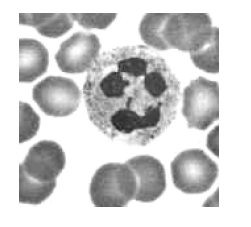

Ao realizar um exame de esfregaço sangüíneo, é observada uma pequena massa de cromatina, na forma de baqueta de tambor, em um dos lóbulos do núcleo de diversos neutrófilos, como observado na figura abaixo.

Essa formação encontrada pode ser classificada como: